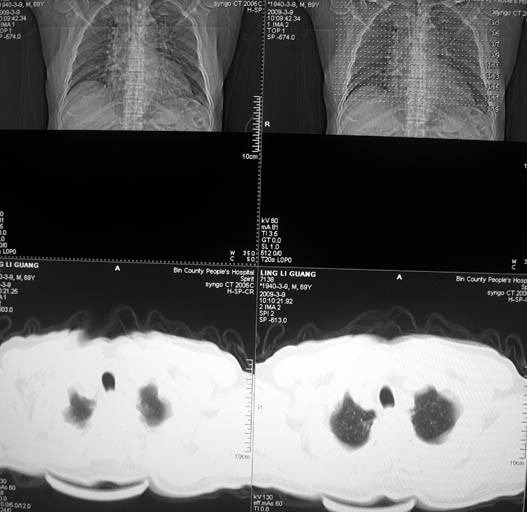

以下是引用随光逐影在2009-3-9 21:36:00的发言:[br]1)两肺上叶尖段结节状病灶,性质待定(不排除肿瘤可能);建议追踪复查。2)右肺中叶内侧段炎症。